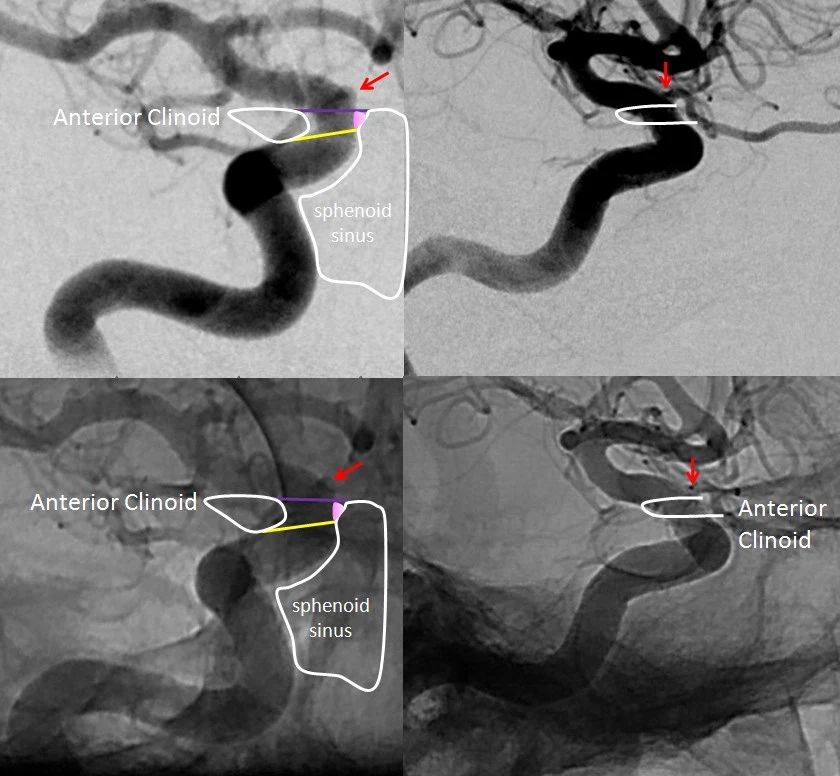

1996年Bouthillier等提出颈内动脉新的分段法,是以数字(C1-C7)顺血流方向标记颈内动脉全程,并考虑到对神经外科具有重要意义的颈内动脉四周解剖。

该分段法各段的解剖分界明确,共分为七段:

C1颈段(Cervical segement)

C2岩段(Petrous segment),

C3破裂(孔)段(Lacerum segment)

C4海绵窦段(Cavenous segement)

C5床段(Clinic segment)

C6眼段(OPhtalmic segement)

C7交通段(Communicating segment)

Bouthillier 分段法:

除C1走行于颈部,归于颈段外;其余各段或走行于颅底骨性结构内,或位于颅内,通称为颅段颈内动脉。

对颈内动脉的理解,可能最大的困难在于颈内动脉的转折弯曲太多,虹吸弯和膝部让人迷乱。

我觉得可以这么来理解。颈内动脉从颈总动脉发出,到最终达到前床突内上方的分叉处,总的走行趋势是向上,向前,向内。